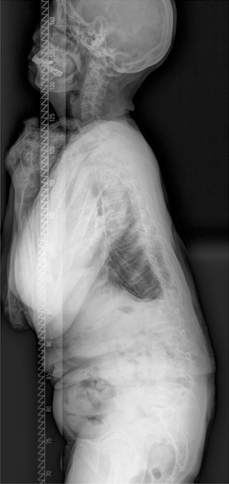

주로 축성 골격을 침범하고, 천장관절을 침범하여 천장 관절염을 유발하며 통상 청소년기 후반에 증세의 발현이 시작되는 경우가 흔하고, 40세 이후의 증상 발현은 매우 드뭅니다. 남녀의 성비는 2~3:1의 비율로 남성에서 많습니다. 가장 특징적인 조기 증상은 만성적인 요추부 동통 및 강직이고, 요부 강직은 특히 아침에 가장 심해지고 더운 목욕이나 강한 육체적 운동으로 호전되는 것이 특징적입니다. 통증은 요추부에서 상부 흉추부, 경추부로 이동하며 강직이 수반되고 완전 강직이 된 후에는 통증이 어느 정도 사라지게 됩니다. 질병이 진행될수록 동통으로 인하여 정상적인 자세를 취하기 어려워져 웅크리는 자세로 강직되며 요추부는 전만곡이 소실되고 흉추부는 후만이 증가되며 경추부도 전만이 소실되어 심한 경우에는 턱과 가슴이 붙을 정도의 심한 변형이 발생되고 따라서 전방 주시가 불가능하여 외출 시 사고의 위험성이 많고 불량한 외적인 자세로 인하여 사회적인 생활에 상당한 어려움을 초래하게 됩니다. 초기 방사선 소견으로는 천장 관절면의 불분명과 전방 척추체의 사각화가 관찰되며 질병이 진행됨에 따라 천장 관절의 골성 유합, 전종인대 및 후종인대의 골화가 이루어지고 방사선 사진 상 마치 대나무 같다고 하여 이를 죽상 척추(bamboo spine)라고 칭하기도 합니다.

정상적으로 흉추는 기립 측면상에서 20~45도의 후만을 이루고 있습니다. 흉추 후만의 첨부는 제 7 흉추에 위치하며 흉추 후만각은 Cobb 방법상 제 4~12 흉추 사이의 각도를 측정합니다. 일반적인 방사선적 진단 기준으로 Schmorl 결절, 불규칙한 척추 종판, 추간판 간격의 협소를 동반한 적어도 3개 이상의 인접 척추의 5도 이상 설상변형이 제시됩니다. 척추 후만은 경직성으로 신전 시에도 변형이 남아 있으며 신전 시 측면 사진을 이용하여 만곡의 경직도를 가늠할 수 있습니다. 전후방 사진상 다양한 정도의 측만이 환자의 약 1/3에서 동반되어 있으며 척추 전방전위증이 동반된 경우도 있습니다. 동반된 척추 전방전위증은 대부분 협부형으로 대상성 요추 과전만으로 인한 추궁 협부의 긴장으로 설명됩니다. 변형의 유형에 따라 흉추형과 흉요추형으로 나눌 수 있으며 흉추형인 제 1형이 더 흔한 형으로 만곡의 첨부가 제 6~8 흉추 사이에 위치하며 흉추 후만증과 함께 경추와 요추의 과전만을 보이고, 흉요추형인 제 2형은 보다 드물며 만곡의 첨부가 제 10 흉추와 제 1 요추 사이에 위치한 흉요추부나 요추부의 후만증을 보입니다. 흉요추형이 보다 유연한 만곡을 가지며 늑골의 지지가 없으므로 만곡이 진행하는 경향을 보입니다.